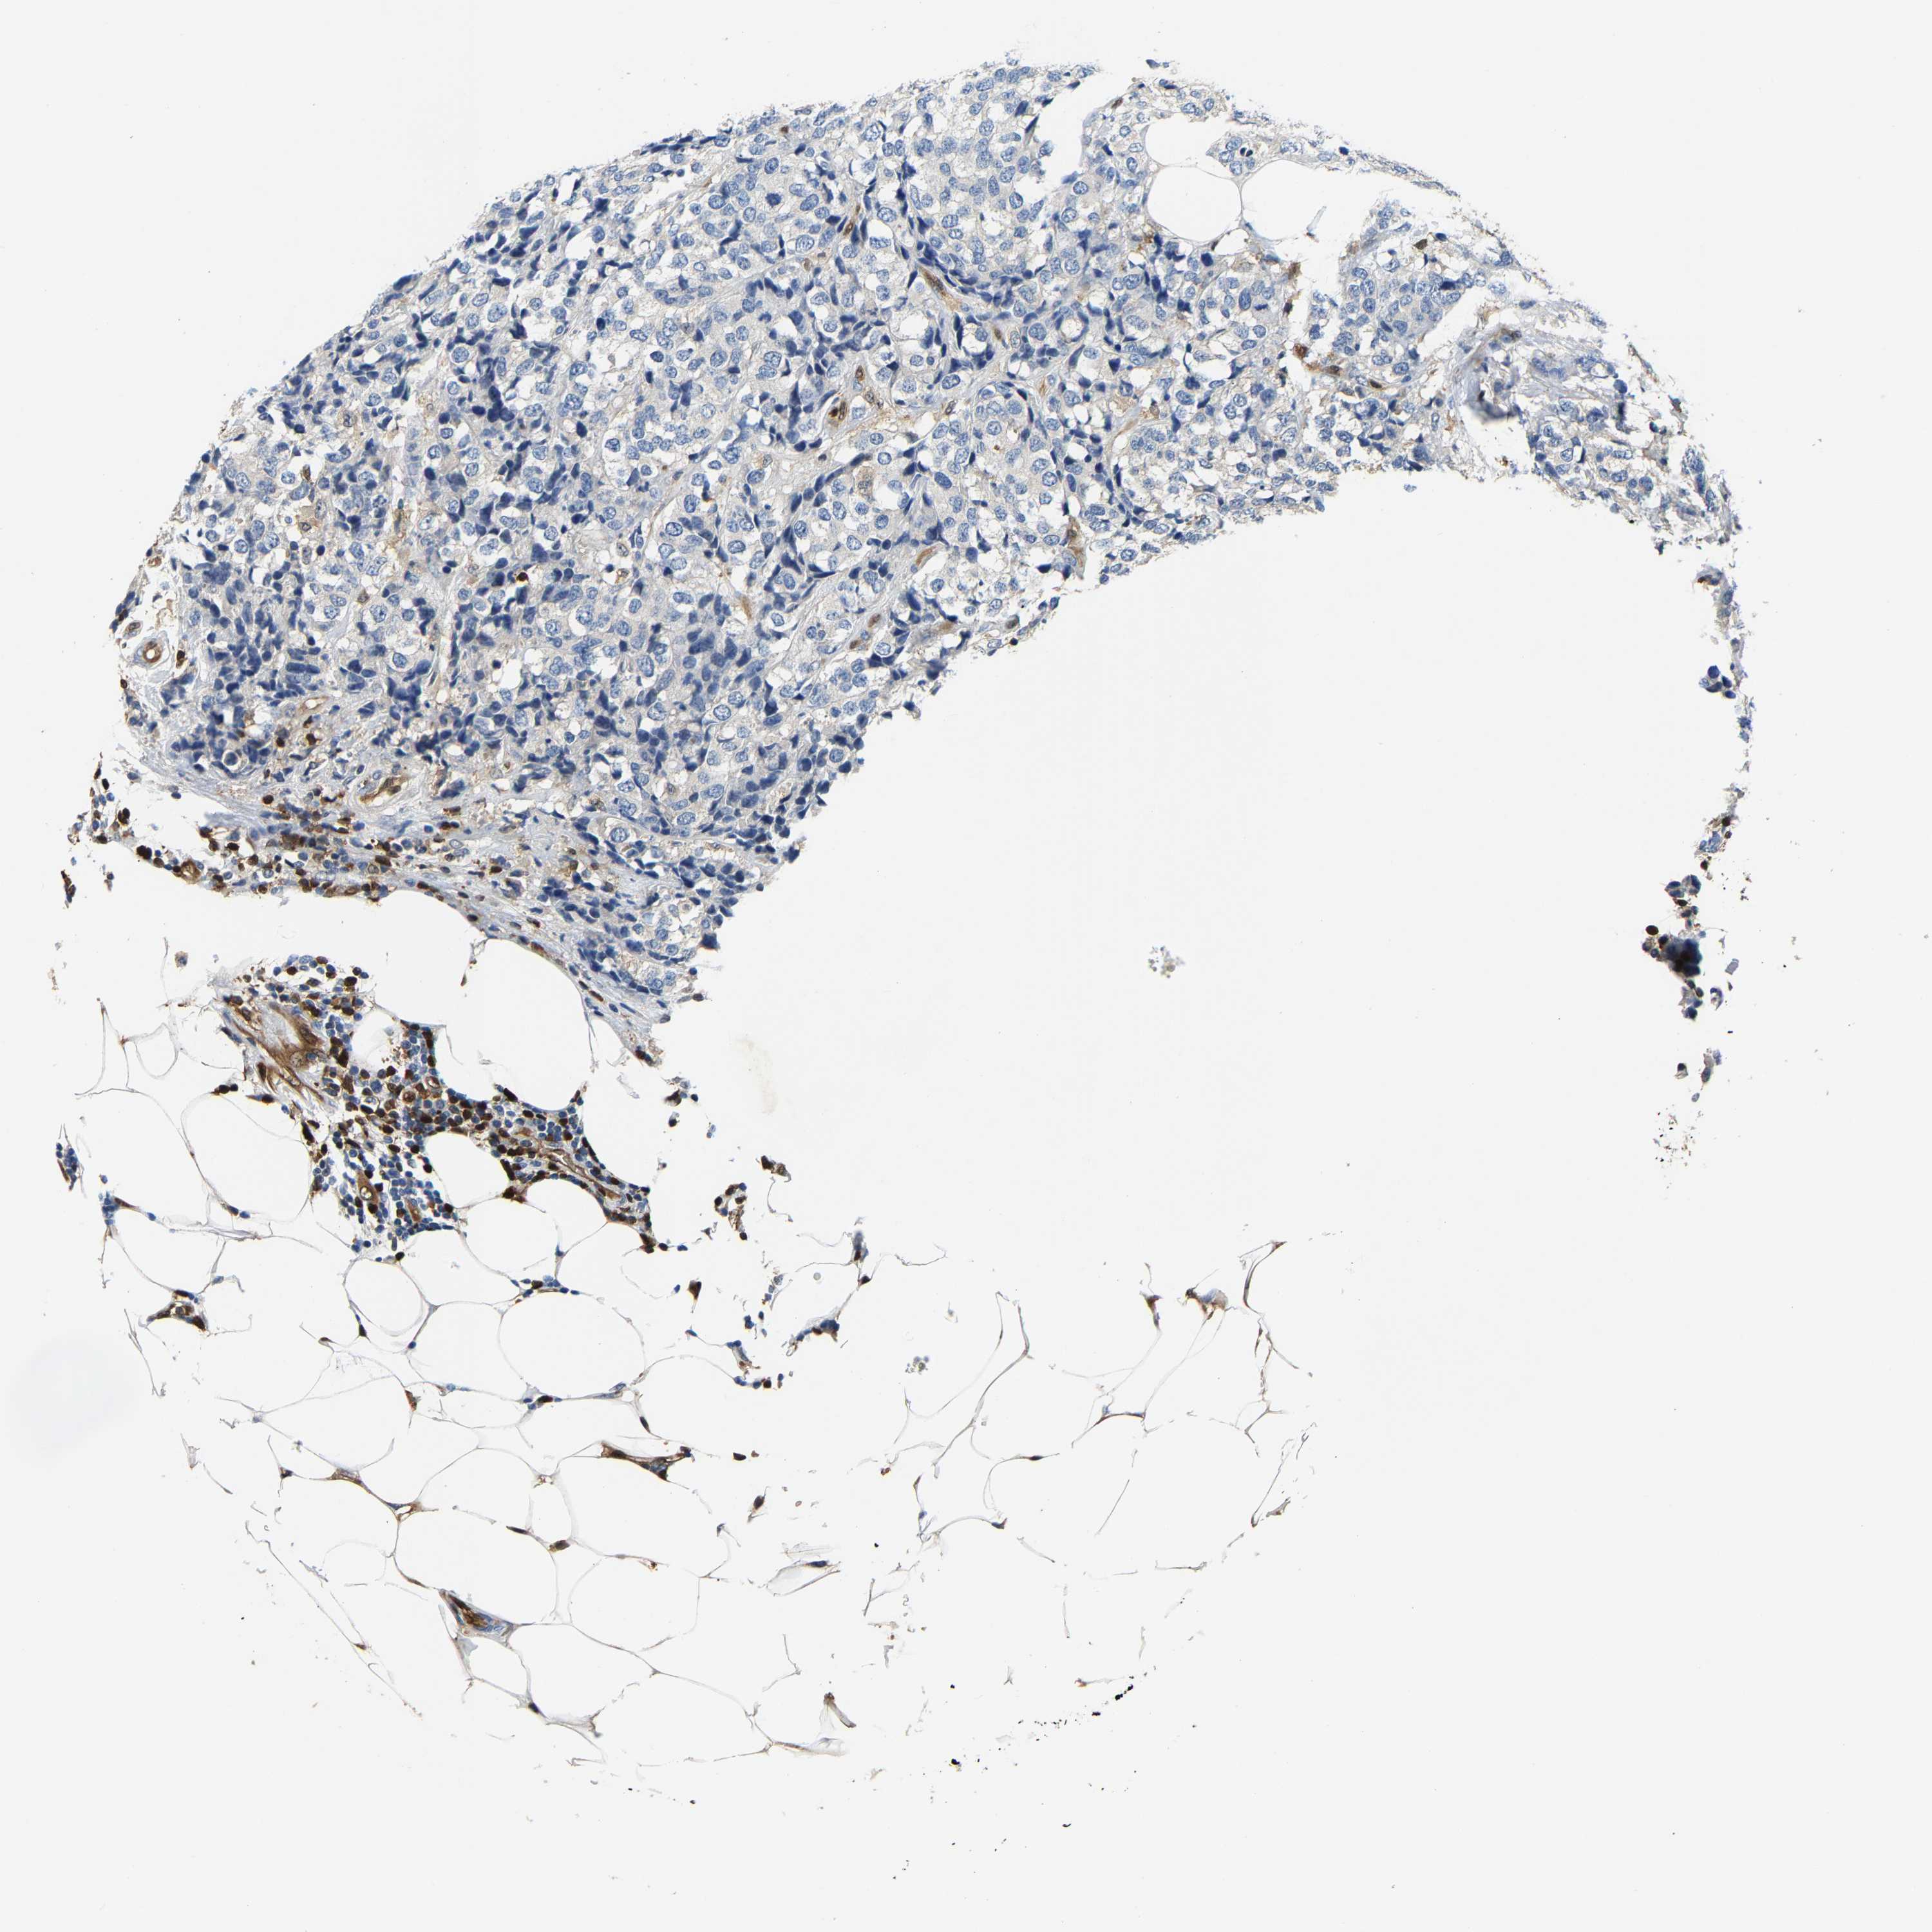

CANCER BREAST CANCER Show tissue menu

BRCA TCGA BRCA VALIDATION PROTEIN EXPRESSION

Breast cancer

Human cancer